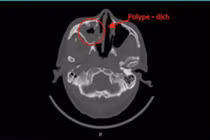

Kết quả chụp hình ảnh học xác định bệnh nhân bị viêm đa xoang nghi do nấm xâm lấn, đã có biến chứng lan sang ổ mắt và thần kinh thị. Đây là tình trạng cực kỳ nguy hiểm, có thể dẫn đến mù lòa, thậm chí đe dọa tính mạng nếu không được xử trí kịp thời.

Ê-kíp phẫu thuật Tai Mũi Họng tiến hành ca mổ nội soi chức năng mũi xoang kéo dài gần 4 tiếng đồng hồ. Trong quá trình phẫu thuật, các bác sĩ đã mở rộng các xoang, lấy sạch các mảng nấm, cắt bỏ hoàn toàn mô hoại tử ở vùng ổ mắt trái và đốt động mạch sàng trước đã bị tắc. Toàn bộ mô bệnh phẩm được gửi đi làm giải phẫu bệnh để kiểm tra chính xác mức độ xâm lấn của nấm.